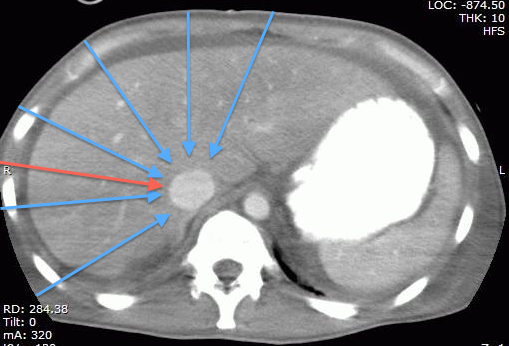

Technical Pearl: the part of the IVC we generally assess being the intrahepatic segment, it is possible to find it almost by scanning through any part of the liver, which happens to provide a great acoustic window. This may be particularly useful when the epigastric area is difficult to access (incision/bandage, drains, in the OR, etc…) or when there is bowel gas in the epigastrium. The figures below show the same IVC, first in a “traditional” epigastric view, then in a view approximately along the plane of the red arrow on the CT scan.